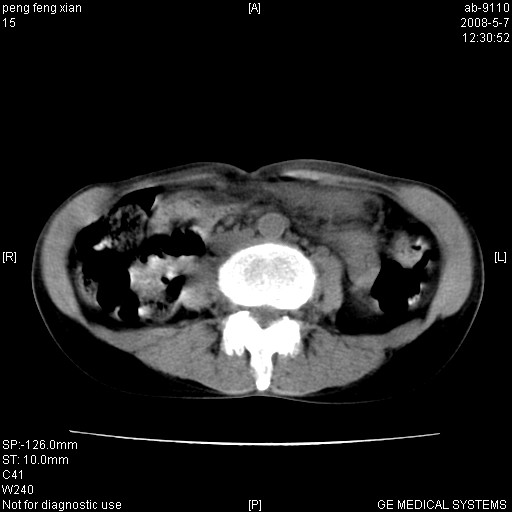

女,56岁。b超左一腹包块,考虑胃肠道肿瘤。

结肠病变?建议行全消化道检查!

胃底占位待出;右肾结石?

胃体部胃壁增厚,不均匀性强化,与胰腺分解欠情.

考虑:胃癌,胰腺受侵待除外.

鉴别:胃淋巴瘤(强化不明显)

建议:胃镜检查.